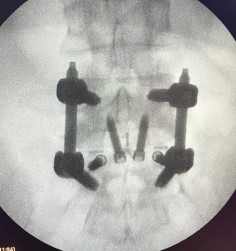

Proceso de fusión completado en un período de hasta 12 meses, con seguimiento radiológico.